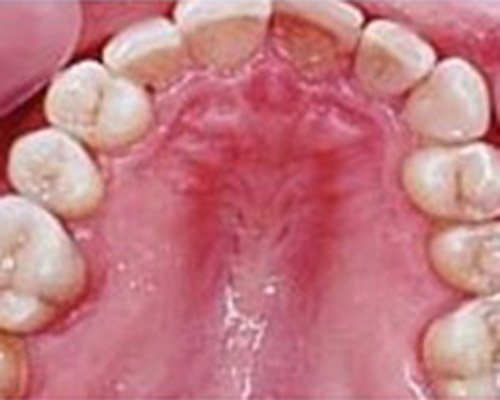

Gentle and painless treatment of dental caries and dental lesions using the most modern techniques and materials from renowned companies with emphasis on aesthetics and functional tooth restoration.

We produce photocomposite, ceramic (inlay, onlay) and amalgam fillings of the latest generations.

When removing old amalgam fillings, we follow all safety instructions to absolutely eliminate risks for the patient and treatment staff.